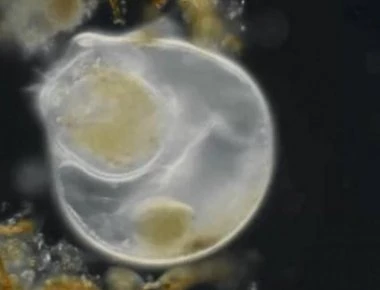

Γυναίκα βρήκε τον φακό επαφής της κρυμμένο στο βλέφαρο μετά από 28 χρόνια!

Πριν από περίπου τρεις δεκαετίες, ένα 14χρονο κορίτσι στην Αγγλία χτύπησε το μάτι της σε έναν αγώνα αντιπτέρισης και έχασε τους φακούς επαφής της. Θα σκεφτείτε, σιγά το πράγμα. Τι θα λέγ...